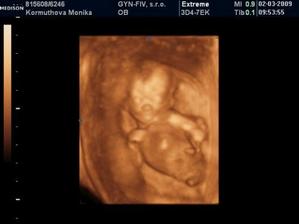

Naše 3D